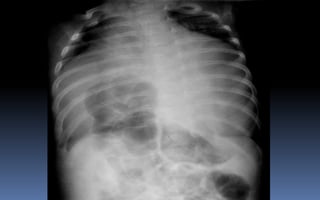

OBSTRUCCION DE ILEON